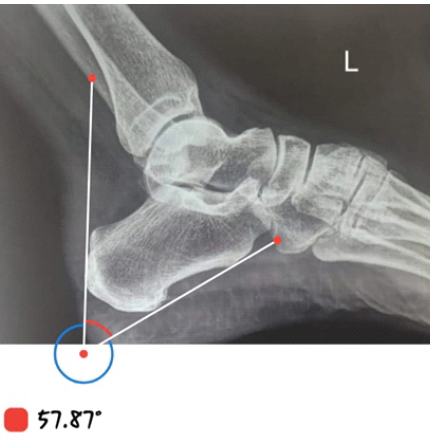

A case series of 10 patients, with 7 female and 3 male patients, with a mean age of 42 years (range 36–50). All patients reported chronic posterior heel pain unresponsive to over 3 months of conservative therapy [3] (Table 1). Radiological confirmation was obtained in each case using Fowler’s angle and presence of parallel pitch lines as shown in Fig. 1 & 2 [1,9].

Figure 2: Pre-operative lateral X-ray showing bony prominence (Fowler’s angle: 58°). Pre-Op X-ray. Fowler’s angle: 58.